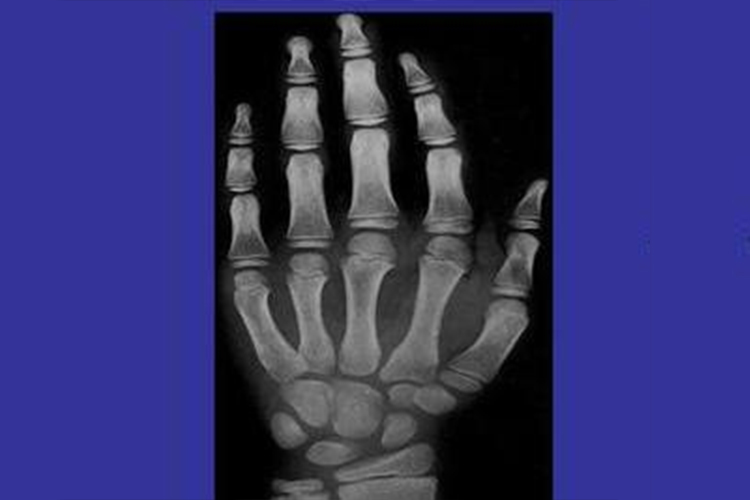

九岁男孩和女孩的骨龄测量影像与十岁测量大体相同,其影像学表现存在区别,具体如下:

九岁男孩

指骨:拇指远端指骨近端面凹陷,第2-5近端指骨骨骺宽度仍小于干骺端的宽度,中间指骨骨骺中间部位增厚,近端面中心部位凸起,远端面扁平,第2-5远端指骨骨骺宽度大于干骺端宽度。

掌骨:第1掌骨骨骺稍微凹陷,桡侧端未达到相应骨干的边缘。

腕骨:舟骨头骨面的白线为其掌面缘,大多角骨远侧对应的第1掌骨面稍凹陷,其舟骨面略平,小多角骨的舟骨面略平;豆状骨开始骨化;指骨骨骺宽度小于干骺端的宽度。